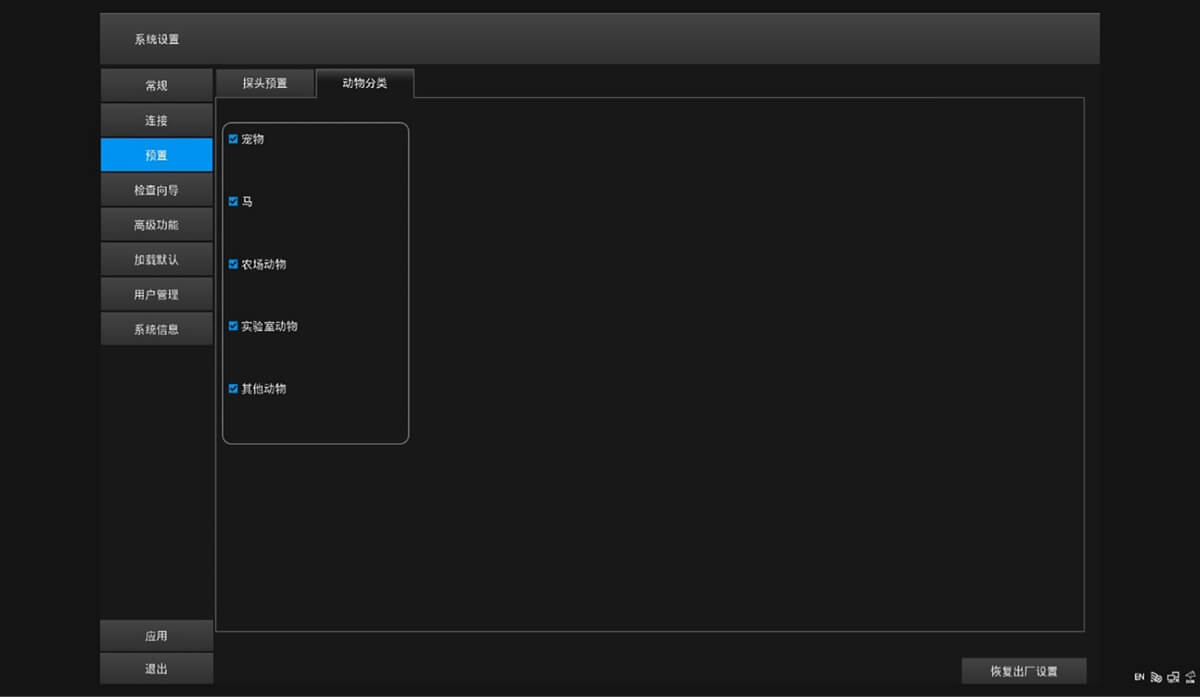

ProPet 60 尊享版

兽用彩色多普勒超声诊断系统